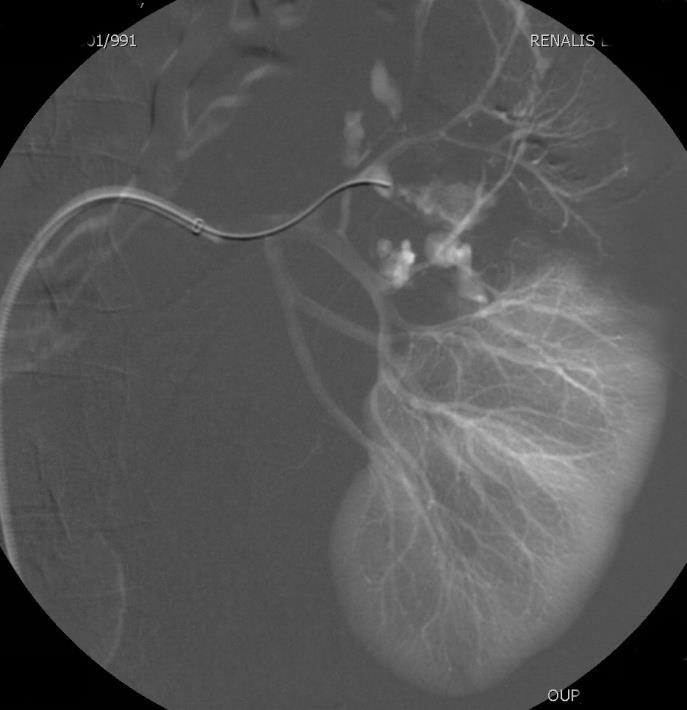

四、肾创伤出血 钝性损伤和穿通伤(最常见医源性损伤,活检、引流和经皮手术等) 血管内治疗适应症 -血流动力学稳定或通过扩容稳定的病人,或外科手术禁忌症患者 -活动性出血、动静脉瘘和假性动脉瘤【1】 血管内治疗技术和并发症 血管内治疗技术和出血发生的部位相关,如主肾动脉损伤采用覆膜支撑架技术,而肾实质发生的假性动脉瘤,动静脉瘘和活动性出血,在考虑微弹簧栓子栓塞。 并发症的发生是罕见的,阻塞远端的肾实质通常会发生梗死。